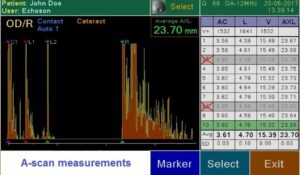

Современный ультразвуковой офтальмологический сканер для визуализации, биометрии и пахиметрии глаза.

Измерение параметров глаза и расчет ИОЛ.

Визуализация структуры глаза.

Измерение толщины роговицы.

Вспомогательный функционал в работе врача.

Сенсорный экран (легкое использование благодаря понятному меню, виртуальная клавиатура для ввода данных пациента); внешняя USB клавиатура (опция), цветной 7″ LCD экран, 800×480 пикселей; десять (10) профилей пользователя; запись изображений на внешний USB накопитель; встроенный термопринтер; легкое обновление программного обеспечения через USB порт; USB порт для внешнего лазерного принтера; 6 типов отчета.